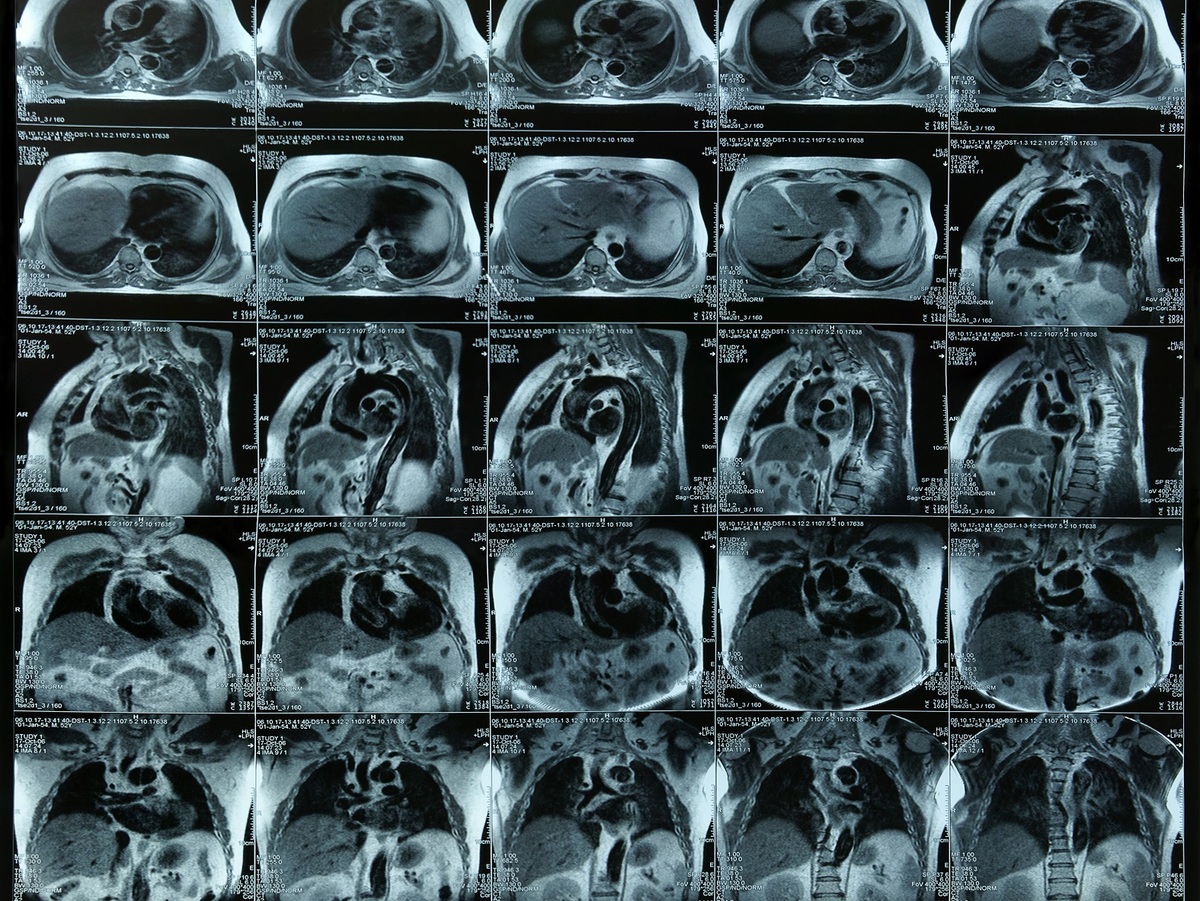

MRI - Chest, Abdomen

What is an MRI of the chest, abdomen or pelvis?

collage of MRI images

Magnetic resonance imaging, or MRI, is a method of producing detailed pictures of organs and body tissues by exposing a patient to radio waves in a strong magnetic field. The field is measured and analyzed by a computer, which forms two- or three-dimensional images that may be viewed on a monitor. Because it uses radio waves and a magnetic field rather than x-rays, there is no exposure to radiation. An MRI of the chest, abdomen or pelvis provides information on the heart and lungs, abdomen and pelvis that may not be detected by an x-ray, ultrasound or computed tomography (CT scan).

Why might my doctor recommend an MRI of the chest, abdomen or pelvis?

An MRI is often used to clarify previous x-rays or CT scans. Your doctor might recommend an MRI of the chest to detect abnormal growths including cancer and the stages of cancer growth. An MRI of the chest also can reveal diseased heart valves, disorders of the ribs and sternum and early breast cancer.